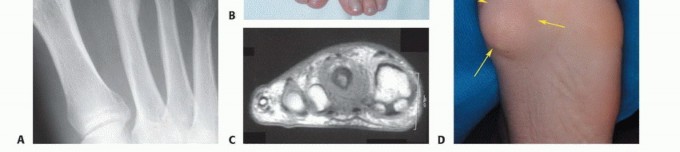

الدراسات التصويرية (Imaging Studies):

- الأشعة السينية (X-rays): هي الخطوة الأولى لتحديد ما إذا كان الورم عظميًا، وتقييم حجمه، وشكله، ومدى تأثيره على بنية العظم.

- التصوير بالرنين المغناطيسي (MRI): يوفر صورًا مفصلة للغاية للأنسجة الرخوة (العضلات، الأوتار، الأعصاب، الأوعية الدموية) والعظام، مما يساعد على تحديد مدى انتشار الورم بدقة، وعلاقته بالهياكل المحيطة. يعتبر التصوير بالرنين المغناطيسي ضروريًا لتخطيط الجراحة.

- التصوير المقطعي المحوسب (CT Scan): يستخدم لتقييم تفاصيل بنية العظام، خاصة في حالات الأورام العظمية، ويمكن استخدامه لتقييم انتشار الورم إلى الرئتين (في حالات الأورام الخبيثة).